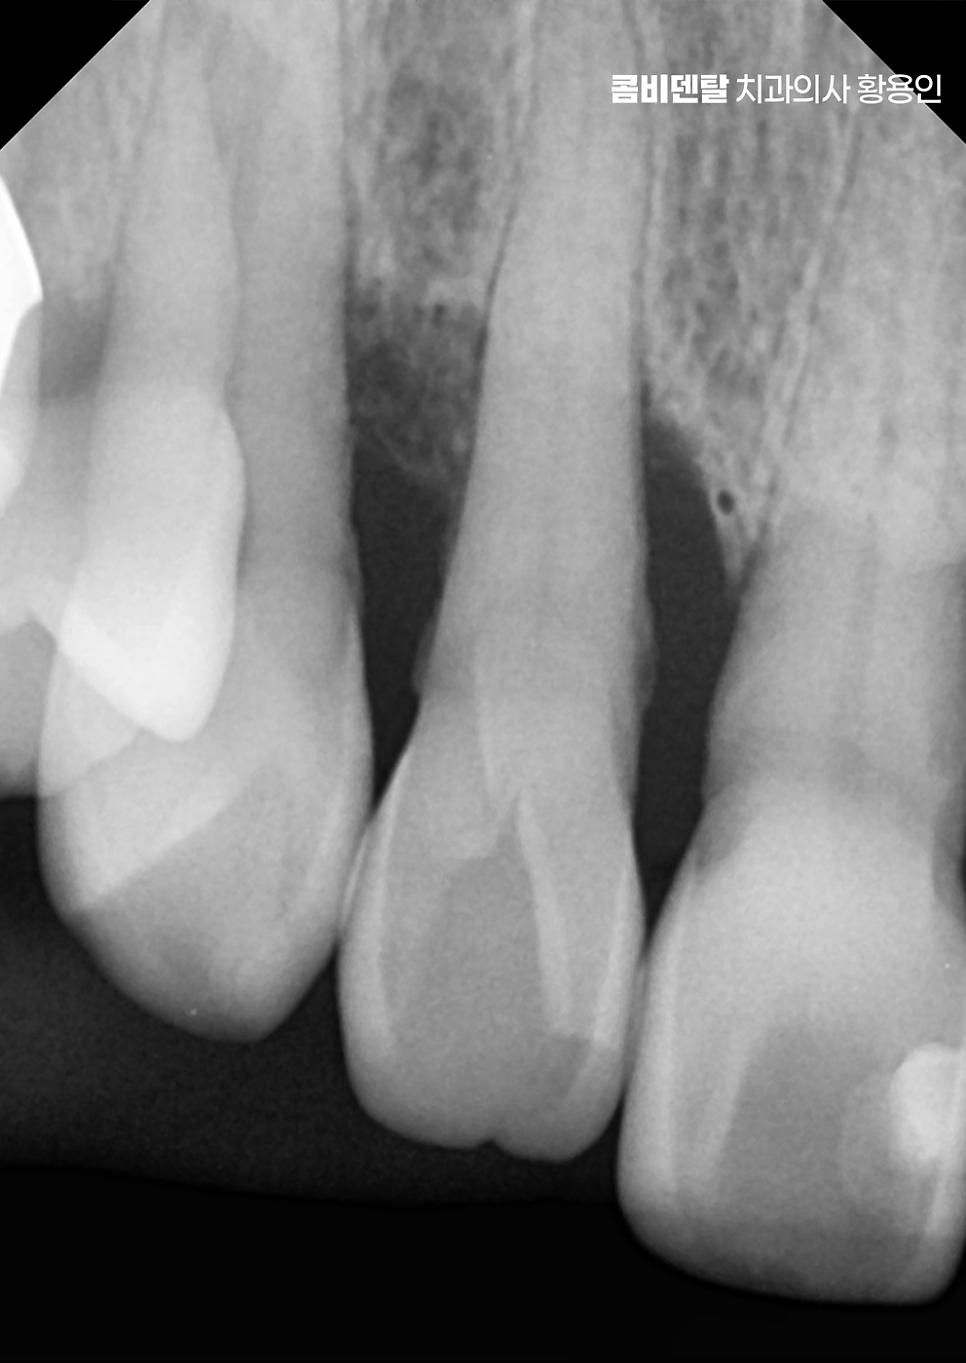

치아 사이가 벌어지는 현상은 보기에는 단순한 틈처럼 느껴질 수 있지만 그 원인이 치주질환 때문이라면 단순히 공간만 메우는 식의 접근으로는 해결되지 않으며 치주질환이라는 건 치아를 지탱하고 있는 잇몸과 치조골, 그러니까 잇몸 뼈 자체가 서서히 무너져가는 질환이기 때문에, 그 과정에서 심하면 치아가 흔들리고, 치아 사이의 지지가 약해지면서 점점 틈이 벌어지게 되며 이 틈은 시간이 지나면서 점점 더 넓어지고 깊어지는 방향으로 진행될 수 있어요

여기서 기본이 되는 건 스케일링인데 스케일링은 단순히 겉에 붙은 치석을 제거하는 게 아니라, 치아 뿌리 쪽 깊숙한 부위에 붙어 있는 세균성 치태까지 제거해 잇몸 안쪽 염증을 줄이는 데 목적이 있어요. 그런데 잇몸 깊숙이 치석이 침착돼 있거나, 이미 치주낭이라고 하는 염증성 주머니가 형성돼 있다면 단순 스케일링만으로는 부족하고, ‘치근활택술’이라는 보다 깊은 치료가 필요한데 이건 마취 후 치아 뿌리 표면을 매끄럽게 다듬어 세균이 다시 달라붙기 어렵게 만드는 치료로서 이러한 잇몸 치료를 통해 잇몸 조직의 재생을 유도하고, 치아의 흔들림을 줄이게 될 수 있어요

하지만 치조골이 이미 많이 흡수돼서 치아가 흔들리거나 벌어진 틈이 너무 넓은 경우에는 단순한 잇몸 치료만으로는 회복이 어려워지며 이럴 때는 치주외과적 접근이 필요해지며 대표적으로 치주소파술, 치은박리소파술과 같이 보다 심화된 잇몸 치료가 필요할 수 있어요